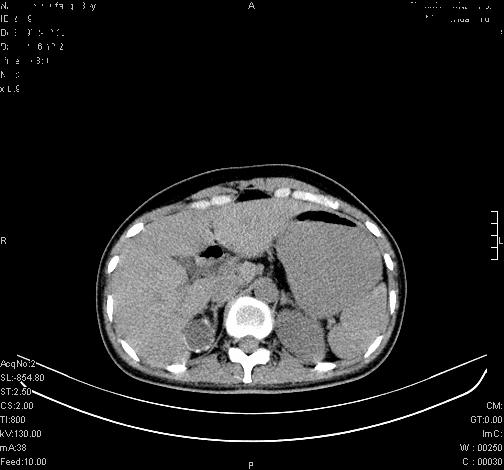

标题: CL0340:【】肾上腺囊肿,比较典型。

患者为年轻女性,查体发现右侧肾上腺囊性占位。无临床体征。

这么漂亮的图像,一看一目了然。典型的右侧肾上腺囊肿,周围有钙化。感谢搂主!

“肾上腺囊肿组织学分为4类:1)内皮细胞性,2)假性囊肿,3)寄生虫性,4)上皮细胞性。其中内皮细胞性最为常见。假性囊肿多为肾上腺内出血后遗留囊腔,囊壁无上皮细胞。寄生虫性多为包虫病引起。上皮性则很少见。”

这么明显的弧形钙化,多考虑包虫病所致的寄生虫性囊肿。

右侧肾上腺囊性密度灶囊壁有钙化。考虑肾上腺囊肿,结核?

右侧肾上腺囊肿,周围有钙化。